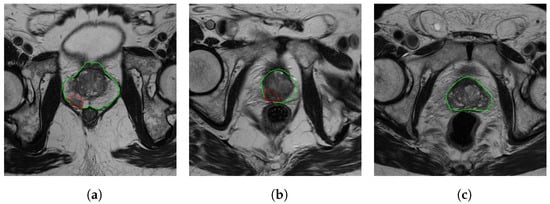

- Cairone, L.; Benfante, V.; Bignardi, S.; Marinozzi, F.; Yezzi, A.; Tuttolomondo, A.; Salvaggio, G.; Bini, F.; Comelli, A. Robustness of Radiomics Features to Varying Segmentation Algorithms in Magnetic Resonance Images. In Proceedings of the Image Analysis and Processing, ICIAP 2022 Workshops, ICIAP 2022; Lecture Notes in Computer Science; Frontoni, P.L.M., Sclaroff, S., Distante, C., Eds.; Springer: Berlin/Heidelberg, Germany, 2022; Volume 13373, pp. 462–472. [Google Scholar] [CrossRef]